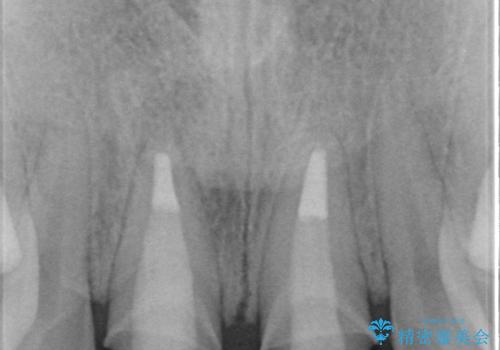

- 3週間後に迫った結婚式までになんとか前歯をきれいにしたいという希望で来院されました。

一回の治療時間を長く取り、限られた時間で最大限の結果を出せるよう集中治療を計画します。

ただ見えるクラウンを白くきれいにするのではなく、長期的な歯の予後を考えると根管治療・ファイバーコア築盛・精密な歯牙形成等クリアすべき条件は多々あると言えます。